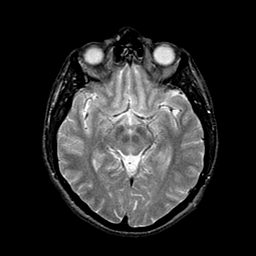

AIDS dementia: overlay -- Slice #7

[Home][Help][Clinical][Tour 1] Slice 7